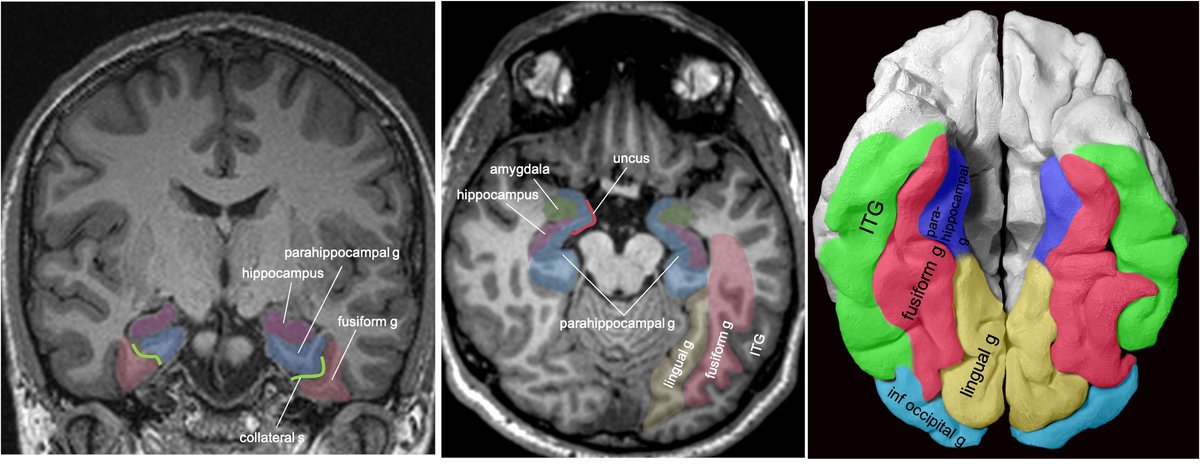

This location can be a bit difficult to describe if you aren’t up on gyral anatomy. Is it med temporal lobe? occipital lobe? limbic? Describing gyral location is more precise, can explain expected symptoms, and clue in future surgical approach.

Gyral anatomy of inf occipitotemporal surface: The inf. temp. gyrus wraps from lateral https://abs.twimg.com/emoji/v2/... draggable="false" alt="➡️" title="Pfeil nach rechts" aria-label="Emoji: Pfeil nach rechts">inferior. The fusiform and lingual gyri span from occipital lobe posteriorly to temporal lobe anteriorly. Parahippocampal is medial temporal (anterior continuation of the lingual g).

https://abs.twimg.com/emoji/v2/... draggable="false" alt="➡️" title="Pfeil nach rechts" aria-label="Emoji: Pfeil nach rechts">inferior. The fusiform and lingual gyri span from occipital lobe posteriorly to temporal lobe anteriorly. Parahippocampal is medial temporal (anterior continuation of the lingual g).

The lingual gyrus is involved in holistic visual and word processing, encoding visual memories, imagery, and dreaming. The ganglioglioma in the shown case is centered in the lingual gyrus.

Fusiform g is just lateral to lingual g on the inf surface of temporal lobe, separated by collateral sulcus. It& #39;s medial to the ITG, separated by ITS. Involved in face and body recognition; word form recognition (on left). (Fusiform g was not definitively involved by tumor). 9/13

Parahippocampal g. is anterior continuation of lingual g. Part of Limbic System. Important in memory encoding and retrieval, visual and social contextualizing.

inferior. The fusiform and lingual gyri span from occipital lobe posteriorly to temporal lobe anteriorly. Parahippocampal is medial temporal (anterior continuation of the lingual g).6/13" title="Gyral anatomy of inf occipitotemporal surface: The inf. temp. gyrus wraps from lateralhttps://abs.twimg.com/emoji/v2/... draggable="false" alt="➡️" title="Pfeil nach rechts" aria-label="Emoji: Pfeil nach rechts">inferior. The fusiform and lingual gyri span from occipital lobe posteriorly to temporal lobe anteriorly. Parahippocampal is medial temporal (anterior continuation of the lingual g).6/13" class="img-responsive" style="max-width:100%;"/>

inferior. The fusiform and lingual gyri span from occipital lobe posteriorly to temporal lobe anteriorly. Parahippocampal is medial temporal (anterior continuation of the lingual g).6/13" title="Gyral anatomy of inf occipitotemporal surface: The inf. temp. gyrus wraps from lateralhttps://abs.twimg.com/emoji/v2/... draggable="false" alt="➡️" title="Pfeil nach rechts" aria-label="Emoji: Pfeil nach rechts">inferior. The fusiform and lingual gyri span from occipital lobe posteriorly to temporal lobe anteriorly. Parahippocampal is medial temporal (anterior continuation of the lingual g).6/13" class="img-responsive" style="max-width:100%;"/>